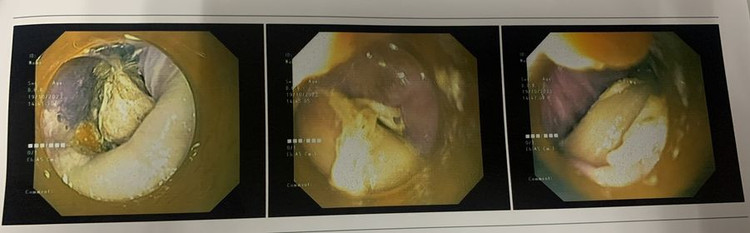

Xương gà 2,5 cm cắm vào thành thực quản tạo ổ áp xe trên phim chụp |

Các bác sĩ khoa Tai Mũi Họng, Gây mê Hồi sức đã thực hiện nội soi thực quản gây mê gắp được dị vật là mảnh xương gà dài 2,5cm. Sau gắp dị vật, người bệnh hết đau, ổn định sức khoẻ, tiếp tục được theo dõi, điều trị tại khoa.

| Xương gà đã được lấy ra |